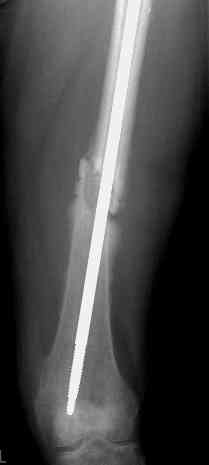

по его наружной поверхности послеоперационный рубец - рана зажила первичным натяжением. При измерении длины бедер обнаружено укорочение левого бедра на 4,5 см. На рентгенограммах этого бедра: ось конечности правильная, отмечается захождение основных костных фрагментов по длине, проксимальный конец штифта выступает слишком медиально и высоко относительно большого вертела, периостальная мозоль незначительна.22.12 - через 6 месяцев после операции, произведенной в ЦРБ, нами по поводу замедленно консолидирующего перелома левой бедренной кости с ее абсолютным укорочением под наркозом произведена операция: удаление штифта, закрытый блокирующий интрамедуллярный остеосинтез перелома левого бедра штифтом без рассверливания (UFN) длиной 40 см, диаметром 10 мм с блокированием только проксимальных отверстий (динамический остеосинтез). Наложен аппарат Илизарова на 4 полукольцах с целью удлинения укороченного бедра. Послеоперационное течение без особенностей. Ежедневно осуществляли дистракцию отломков на 1 мм. Через 3 недели после операции больной выпи-сан на амбулаторное лечение с продолжением дистракции отломков. В течение 1,5

месяцев дистракции укорочение левого бедра удалось полностью устранить. 22.02.00, т.е. через 2 месяца после повторного остеосинтеза, больному произведено дистальное блокирование штифта двумя винтами и демонтирован аппарат Илизарова. В течение 2 недель после операции больной ходил с помощью костылей, потом 2 недели с тростью. Опороспособность и функция оперированной конечности полностью восстановились через 4 недели после операции.

Фиксаторы удалены через 12 месяцев после операции, выполненной по поводу замедленной консолидации перелома бедра с его укорочением.

Спасибо! Истинно мастерская работа. Представляю как счастлив пациент исходом этой истории.

На финальных снимках видно - сращение прям таки железное. Если Вы не устали отвечать, осмелюсь задать еще вопрос - что-то принимал пациент в целях ускорения сроста (кальций, режим питания). Интересны также вопросы восстановления функций конечности - в какой период были рекомендованы группы упражнений для восстановления основных групп мышц?